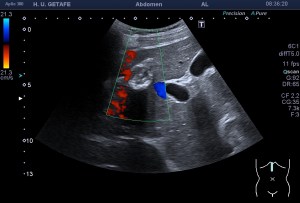

En esta última imagen te muestro la angiogénesis o neovascularización. Existe un aumento de aporte sanguíneo para reparar aquel tejido que está dañado. Esta angiogénesis o aumento de vascularización y por tanto Doppler podría ser secundario a un proceso de reparación mal gestionado por el tejido. Esta angiogénesis también podría estar en relación con aumentos del dolor en la zona y no significa que la patología cure antes. Gracias Javier. Gracias Amigo.